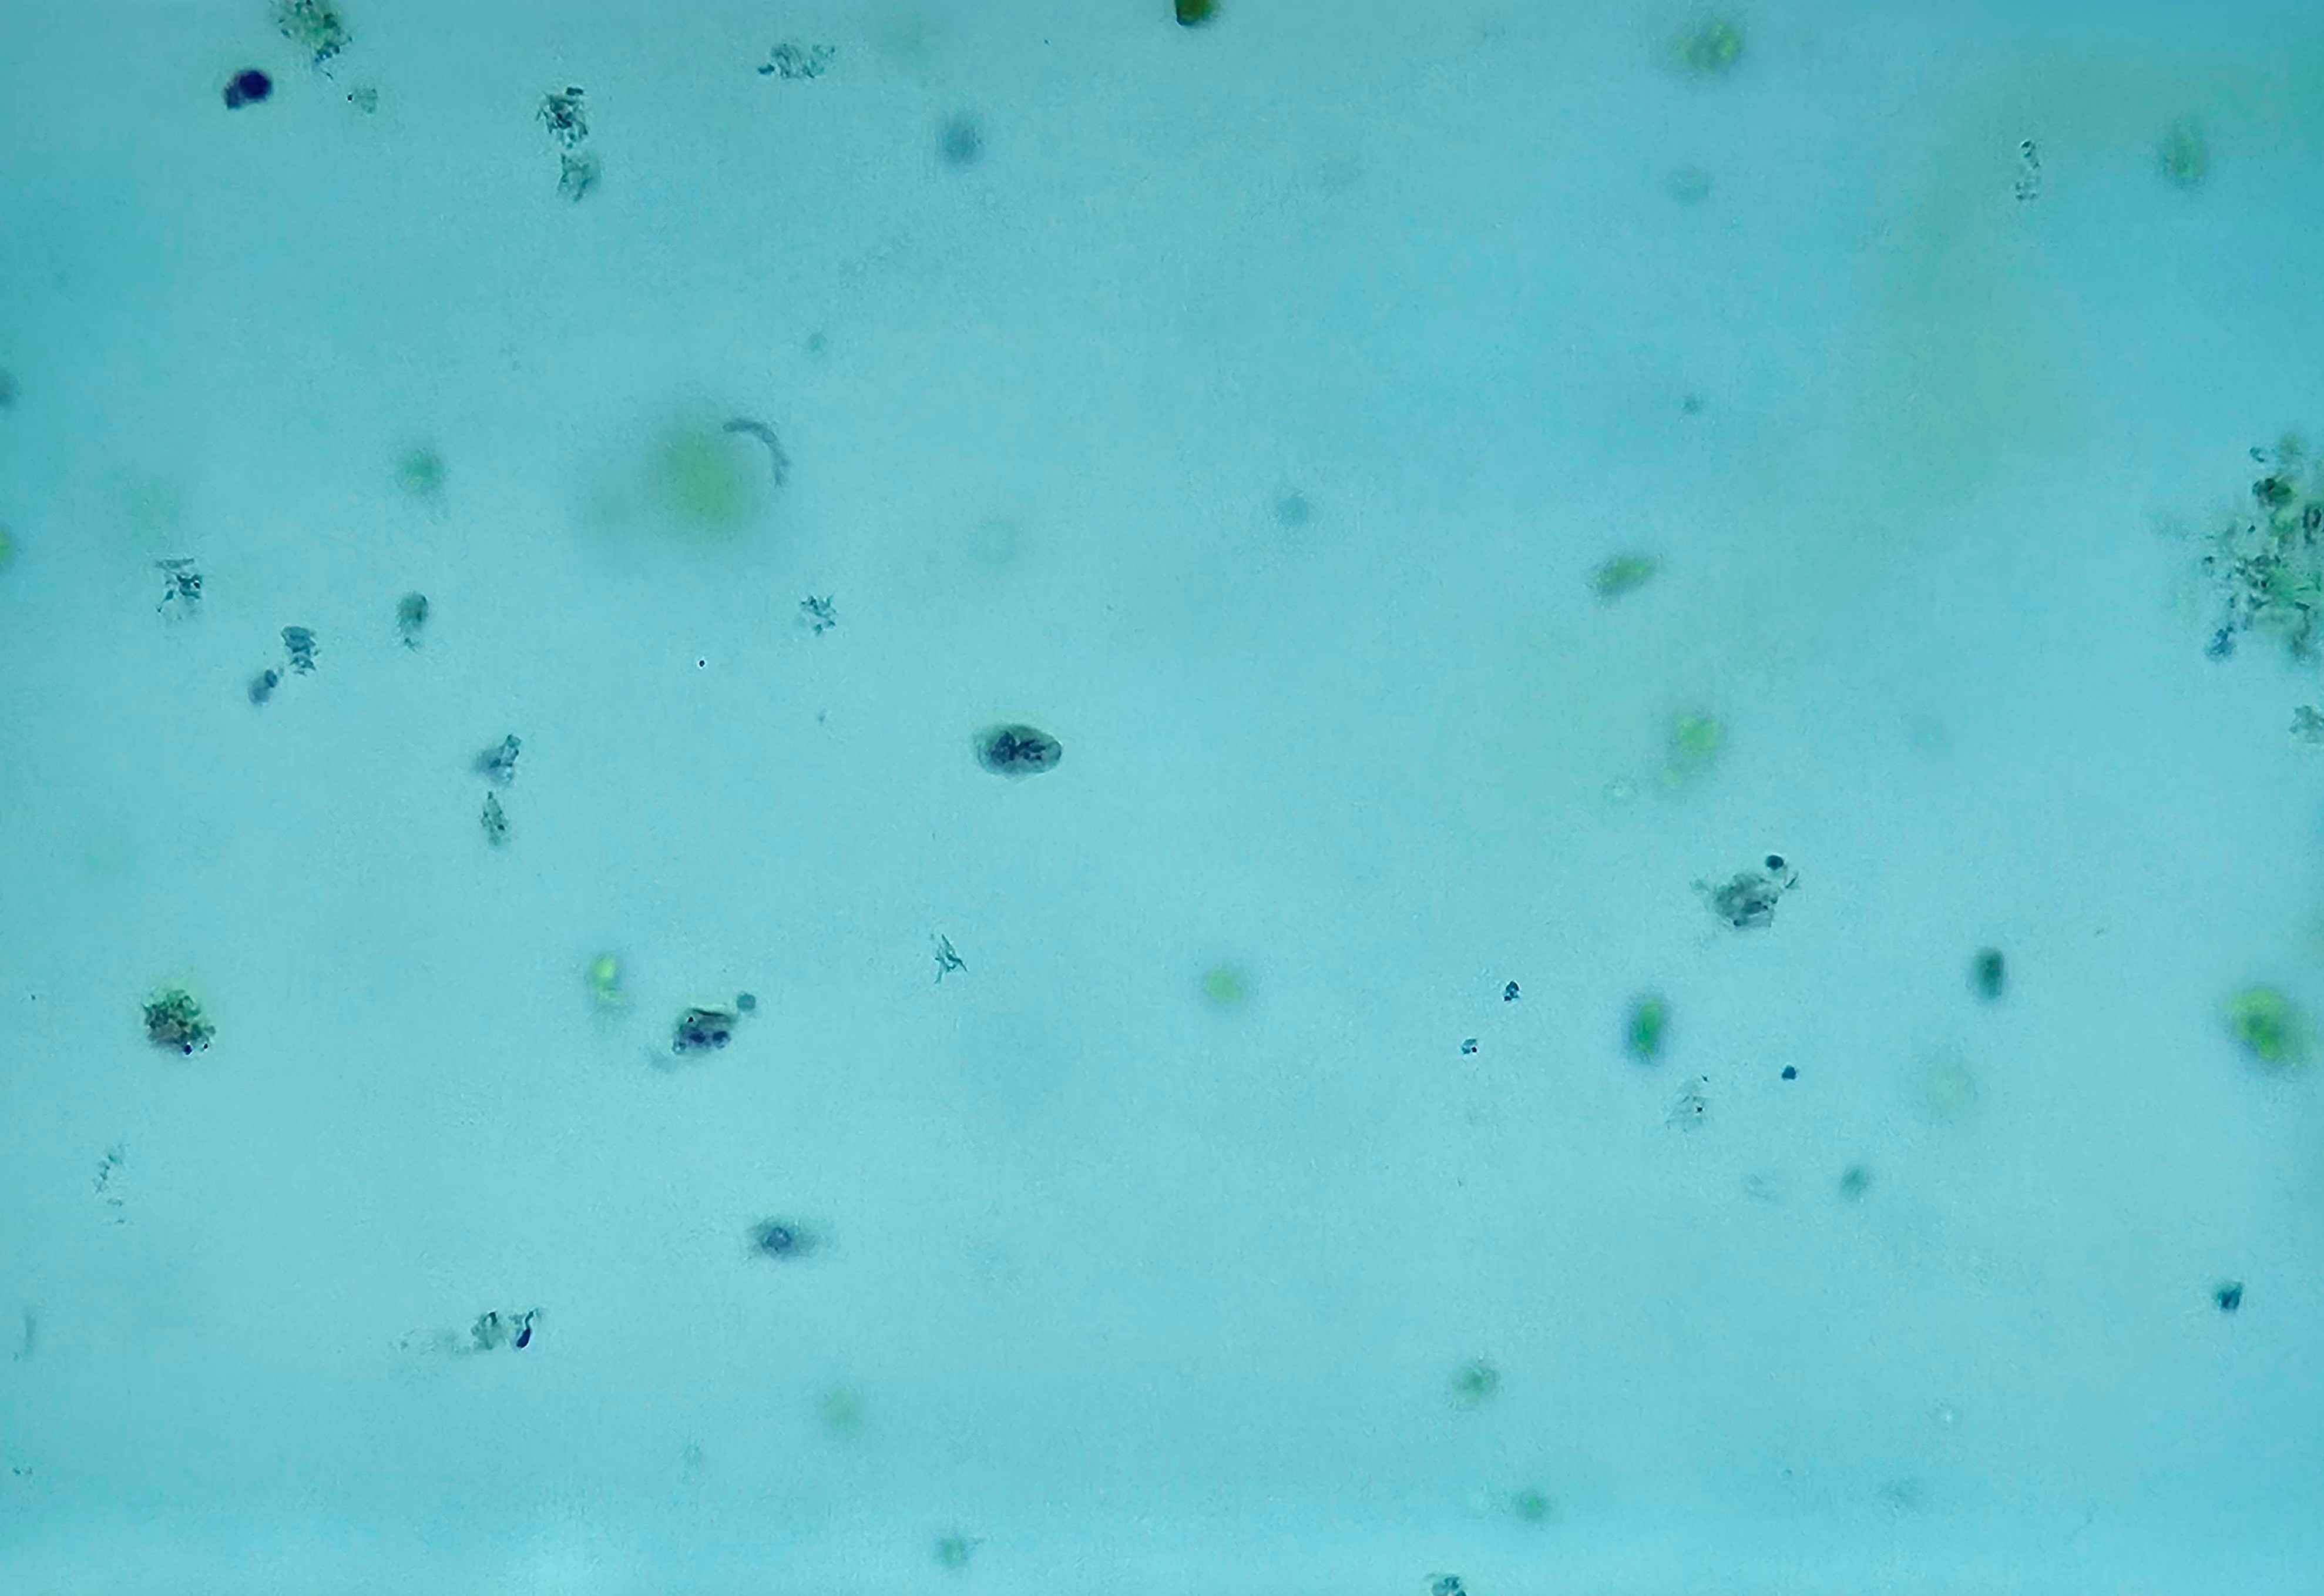

🩸🤖 Plasmodium sp. (śledziona - malaria melanemia)

🧩🦠 Cechy charakterystyczne:

🔴🟡🟢️🟤 - złogi hemosyderyny.

😷❓ Parazytoza: Malaria